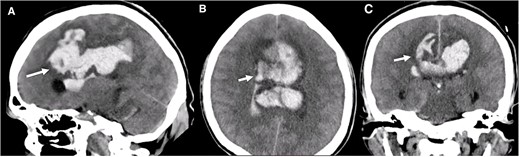

A multislice computed tomography (CT) without contrast revealed an extensive interhemispheric hematoma in the frontoparietal region, subarachnoid hemorrhage, and intraventricular hemorrhage in the adjacent area (Fisher grading score of IV) (Fig. 1). In addition, cerebral angiotomography and 3D reconstruction imaging suggested the presence of two abnormal vascular lesions: (i) a fusiform aneurysm of 12 × 7 mm in an accessory A2 portion of the ACA and (ii) an unruptured saccular aneurysm of 3.3 × 2.8 mm in the distal segment of the basilar artery adjacent to the anterolateral surface of the P1 segment and the left superior cerebellar artery (Figs 2 and 3).

Cerebral angiotomography. (A) Axial cut depicts a midline irregular vascular lesion (yellow circle). (B) Axial cut shows a small saccular aneurysm at the basilar artery (white arrow).